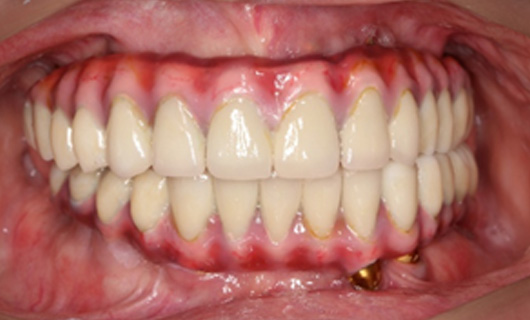

Dentures that are supported by an implant can provide significant improvements in chewing and smiling. In contrast to regular complete dentures, these dentures are horseshoe-shaped reducing bulkiness and creating more space on the palate for better tasting ability. A person with implant-supported dentures can enjoy fruits, vegetables, steaks, corn on the cob, and other foods compared to a person wearing traditional dentures. In addition, implant-support dentures significantly boost patients’ confidence to smile and speak.

- Fabrication of final denture: Once you and your dentist have decided on a final fit and appearance, a dental technician or prosthodontist will construct a final prosthesis that is durable and natural-looking.

- Insertion: Once your final dentures are made, they are fixed to dental implants in the jaw bone.